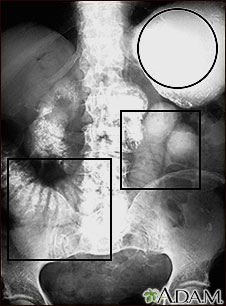

Ileus - X-ray of distended bowel and stomach

This abdominal x-ray shows a stomach filled with fluid and a swollen (distended) small bowel, caused by a blockage (obstruction) in the intestines. A solution containing a dye (barium) that is visible on x-rays was swallowed by the patient (upper GI series).